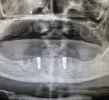

Implant Treatment

Peri-implantitis

Peri-Implant Mucositis